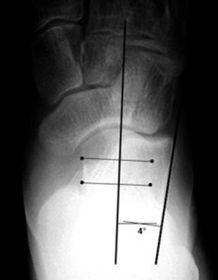

| What angle is this? Is this normal or abnormal? | 1st intermetatarsal angle Abnormal. Greater than 9 degrees is abnormal. Usually due to metatarsus primus varus |

| What deformity is this? | Metatarsus Adductus |